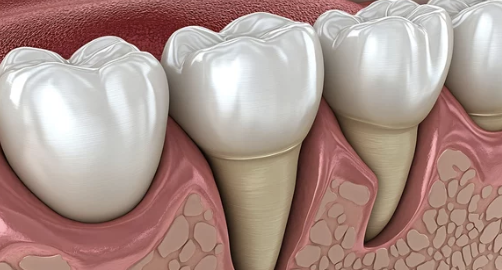

잇몸이 아래로 또는 위로 내려가 치아 뿌리가 드러나는 현상은 치은퇴축(Gingival Recession)이라고 하며, 다음과 같은 다양한 원인으로 발생할 수 있습니다.

잇몸이 한 번 퇴축되면 자연적으로 복원되기는 어렵기 때문에, 조기 진단과 적절한 치료가 매우 중요합니다.

잇몸 퇴축은 서서히 진행되기 때문에 자각하기 어려운 경우가 많지만, 다음과 같은 증상이 나타난다면 반드시 치과 검진이 필요합니다.

- 치아가 예전보다 더 길어 보임

치은퇴축은 심할 경우 치아를 지지하는 치조골까지 손상시켜 결국 치아가 흔들리거나 빠질 수 있습니다.